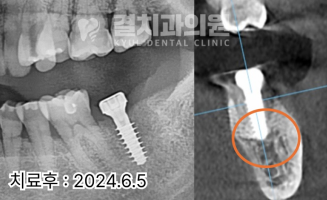

정확한 진단을 위해

파노라마 및 CT 촬영을 진행하였고,

그 결과 뿌리 주변의 뼈가 상당히 흡수된 상태임을

확인할 수 있었습니다.

골흡수가 심한 부위에는 골이식을 병행하여

뼈의 건강을 유지했습니다.

또한, 임플란트의 끝 부위를

남아있는 치조골에 단단히 고정하여

안정성을 높였습니다.